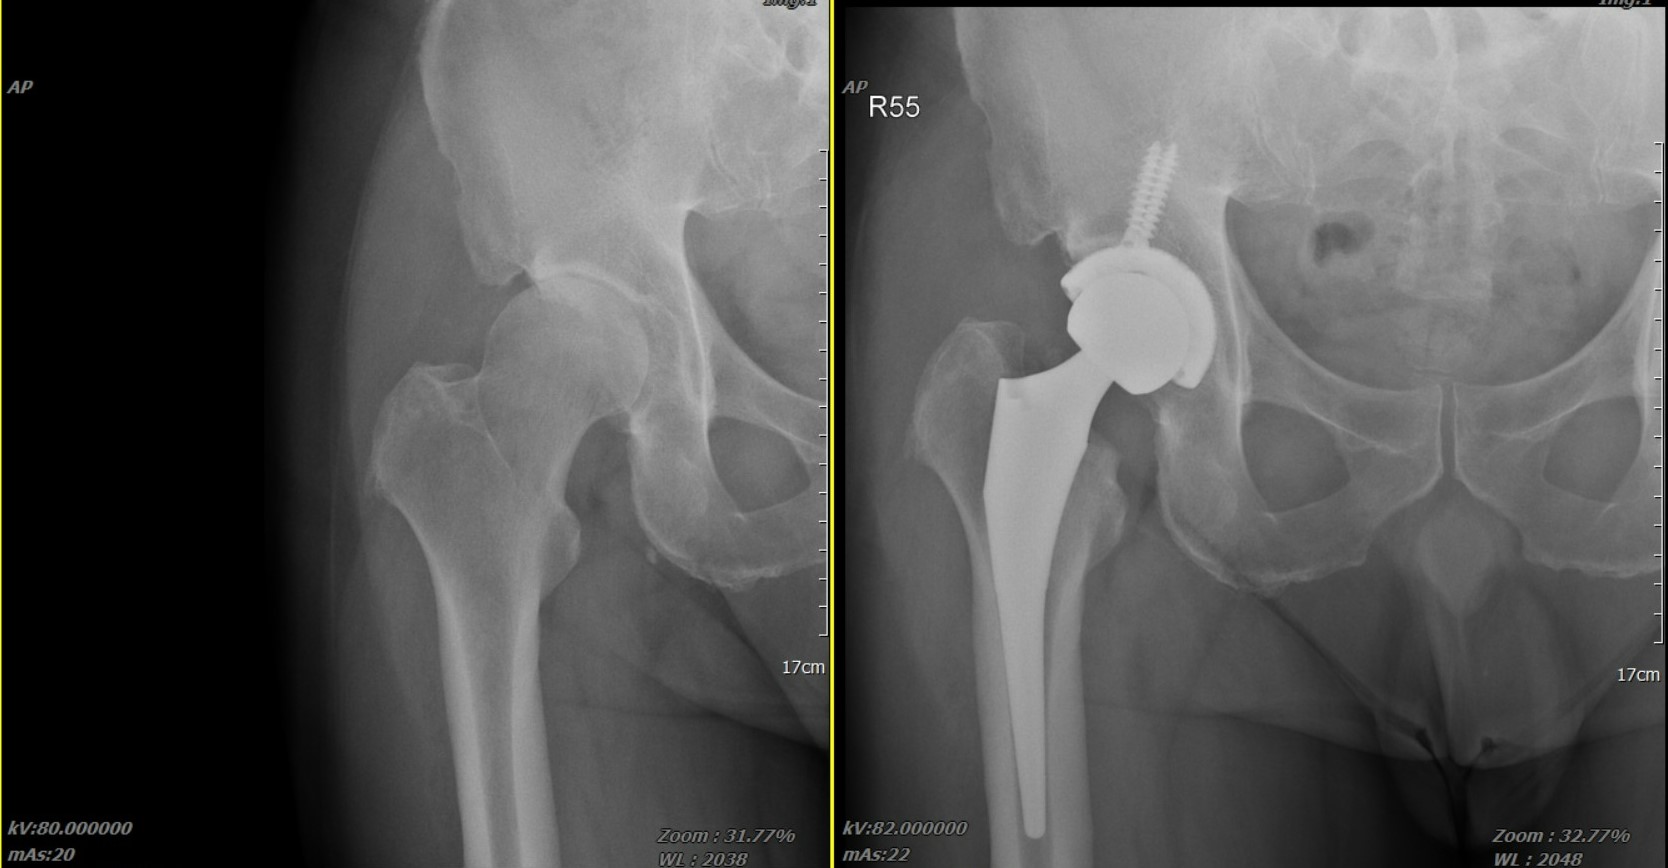

微創人工髖關節手術全攻略:傷口小、免復健、重新大步走路

【文章摘要】如果您發現自己走路髖部隱隱作痛、蹲不下去,甚至連穿鞋襪都覺得吃力,這可能是髖關節在發出訊號。以前的人聽到「換關節」就怕傷口大、脫臼,但現在的「微創 」技術就像是在肌肉縫隙中完成關節置換,不需切斷肌肉,且精準度大幅提升,許多病患甚至「術後當天就能下床」。本文將帶您深度了解微創人工髖關節手術。

手術術式深度對比:傳統vs微創

「傳統」髖關節置換手術和「微創」髖關節置換手術的差別在於,「微創」髖關節置換手術的核心在於「組織保存」,也追求皮膚傷口的縮小,讓病患的恢復過程較輕鬆。根據進入關節的路徑,主要分為以下三種範式: